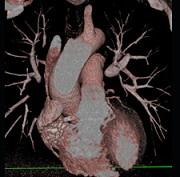

下面一组图像应考虑为 ( )A、左前降支钙化B、左旋支钙化C、正常的左前降支D、右侧冠状动脉钙化E、正常的右侧冠状动脉

问题 下面一组图像应考虑为 ( )

选项 A、左前降支钙化 B、左旋支钙化 C、正常的左前降支 D、右侧冠状动脉钙化 E、正常的右侧冠状动脉

答案 D